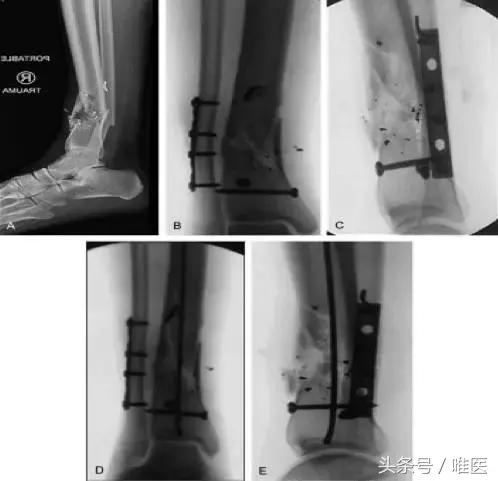

◎ 阻挡钉 阻挡钉可以在导丝放置前,扩髓时,置钉时放置。阻挡钉可以缩窄髓腔内的髓内钉通道。有利于修正成角,使导丝和内植物沿正确的通道通过。(图2)

图2 胫骨远端干骺端高度粉碎性骨折显示向后成角后畸形(A)和腓骨固定后残余内翻畸形(B)尽管校正矢状位向后成角(C)。为了抵消骨折变形,前后位及侧位2枚阻挡螺钉放置在骨折远端部分(B和C)。扩髓置入导丝后进一步纠正冠状面畸形(D),同时保持矢状面平衡(E)。生物力学研究证明阻挡螺钉有助于防止胫骨远端干骺端畸形。当使用阻塞螺钉,外科医生可以使用大号螺丝,或髓内钉的标准交锁螺钉(适应症外使用)。